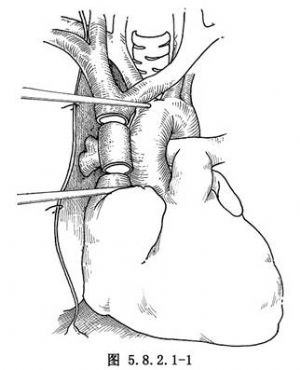

5.切除上腔靜脈前,先解剖和遊離阻塞段上腔靜脈的近心端(上腔-右房接合點)和遠心端(左、右無名靜脈的匯合處),然後各置一把Potts鉗(圖5.8.2.1-1)。

6.上腔靜脈切除後,用18或20號的聚四氟乙烯(PTFE)人造血管與上腔靜脈吻合。先吻合遠心端,用5-0的Prolene線,在上腔靜脈的遠端和人造血管之間縫兩條牽引線,結紮後用連續外翻縫合法,分別縫合前、後壁,打結在血管外面。同樣的方式,吻合近心端(圖5.8.2.1-2)。近心端縫線未打結前,向移置血管內注入肝素鹽水沖洗,然後放開遠端Potts鉗,排淨移置血管內所有空氣,最後移去近端阻斷鉗(圖5.8.2.1-3)。